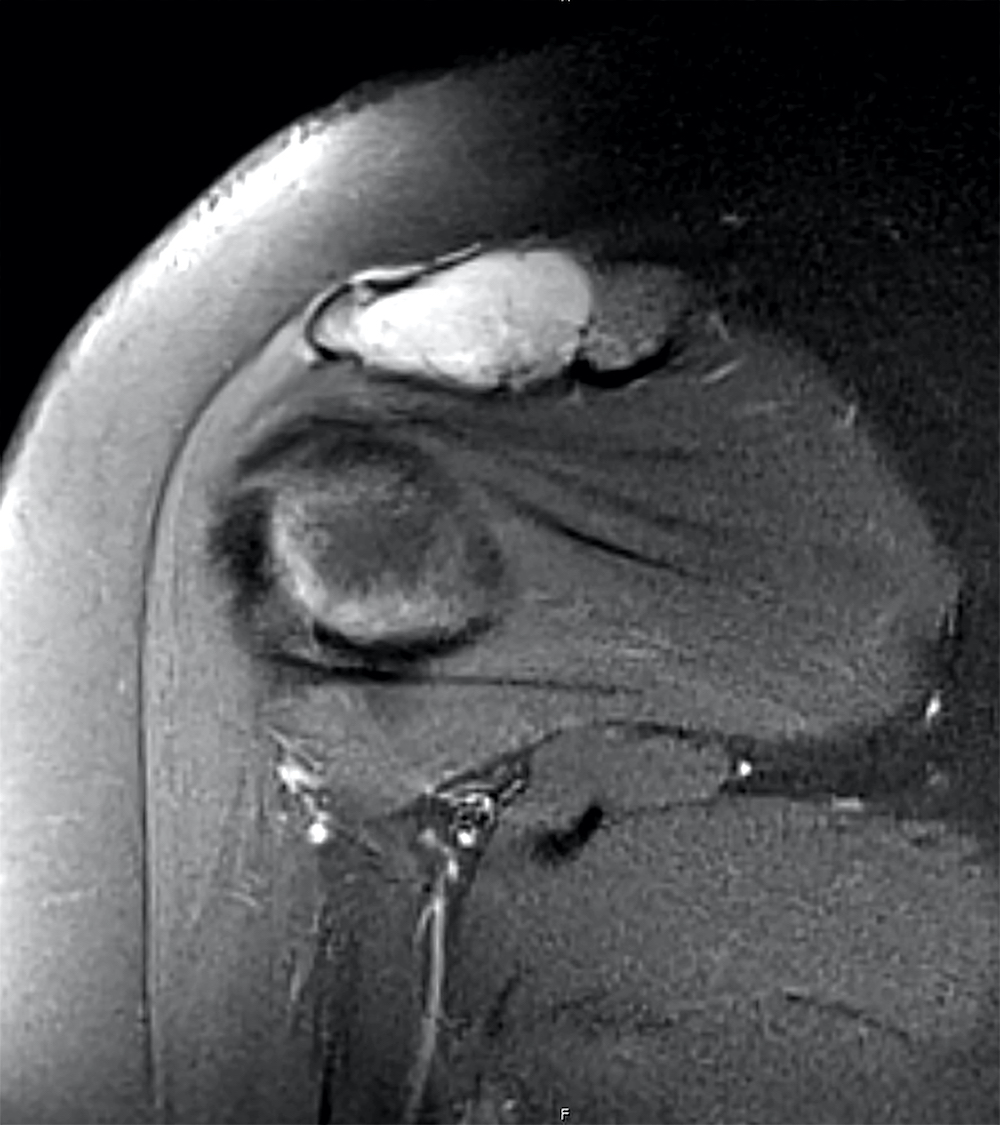

Radiology images

- Xray: well defined lucent lesion with a thin sclerotic rim, with or without matrix calcifications, commonly arising eccentrically within the epiphysis of long bones; extension to the metaphysis can be seen (AJR Am J Roentgenol 1977;128:613)

- CT scan: can show matrix calcification and solid periosteal reaction (J Comput Assist Tomogr 1984;8:907)

- MRI: associated with bone marrow edema, periosteal and soft tissue reactions, varying signal intensity on T2 weighted sequences (Skeletal Radiol 2002;31:88)